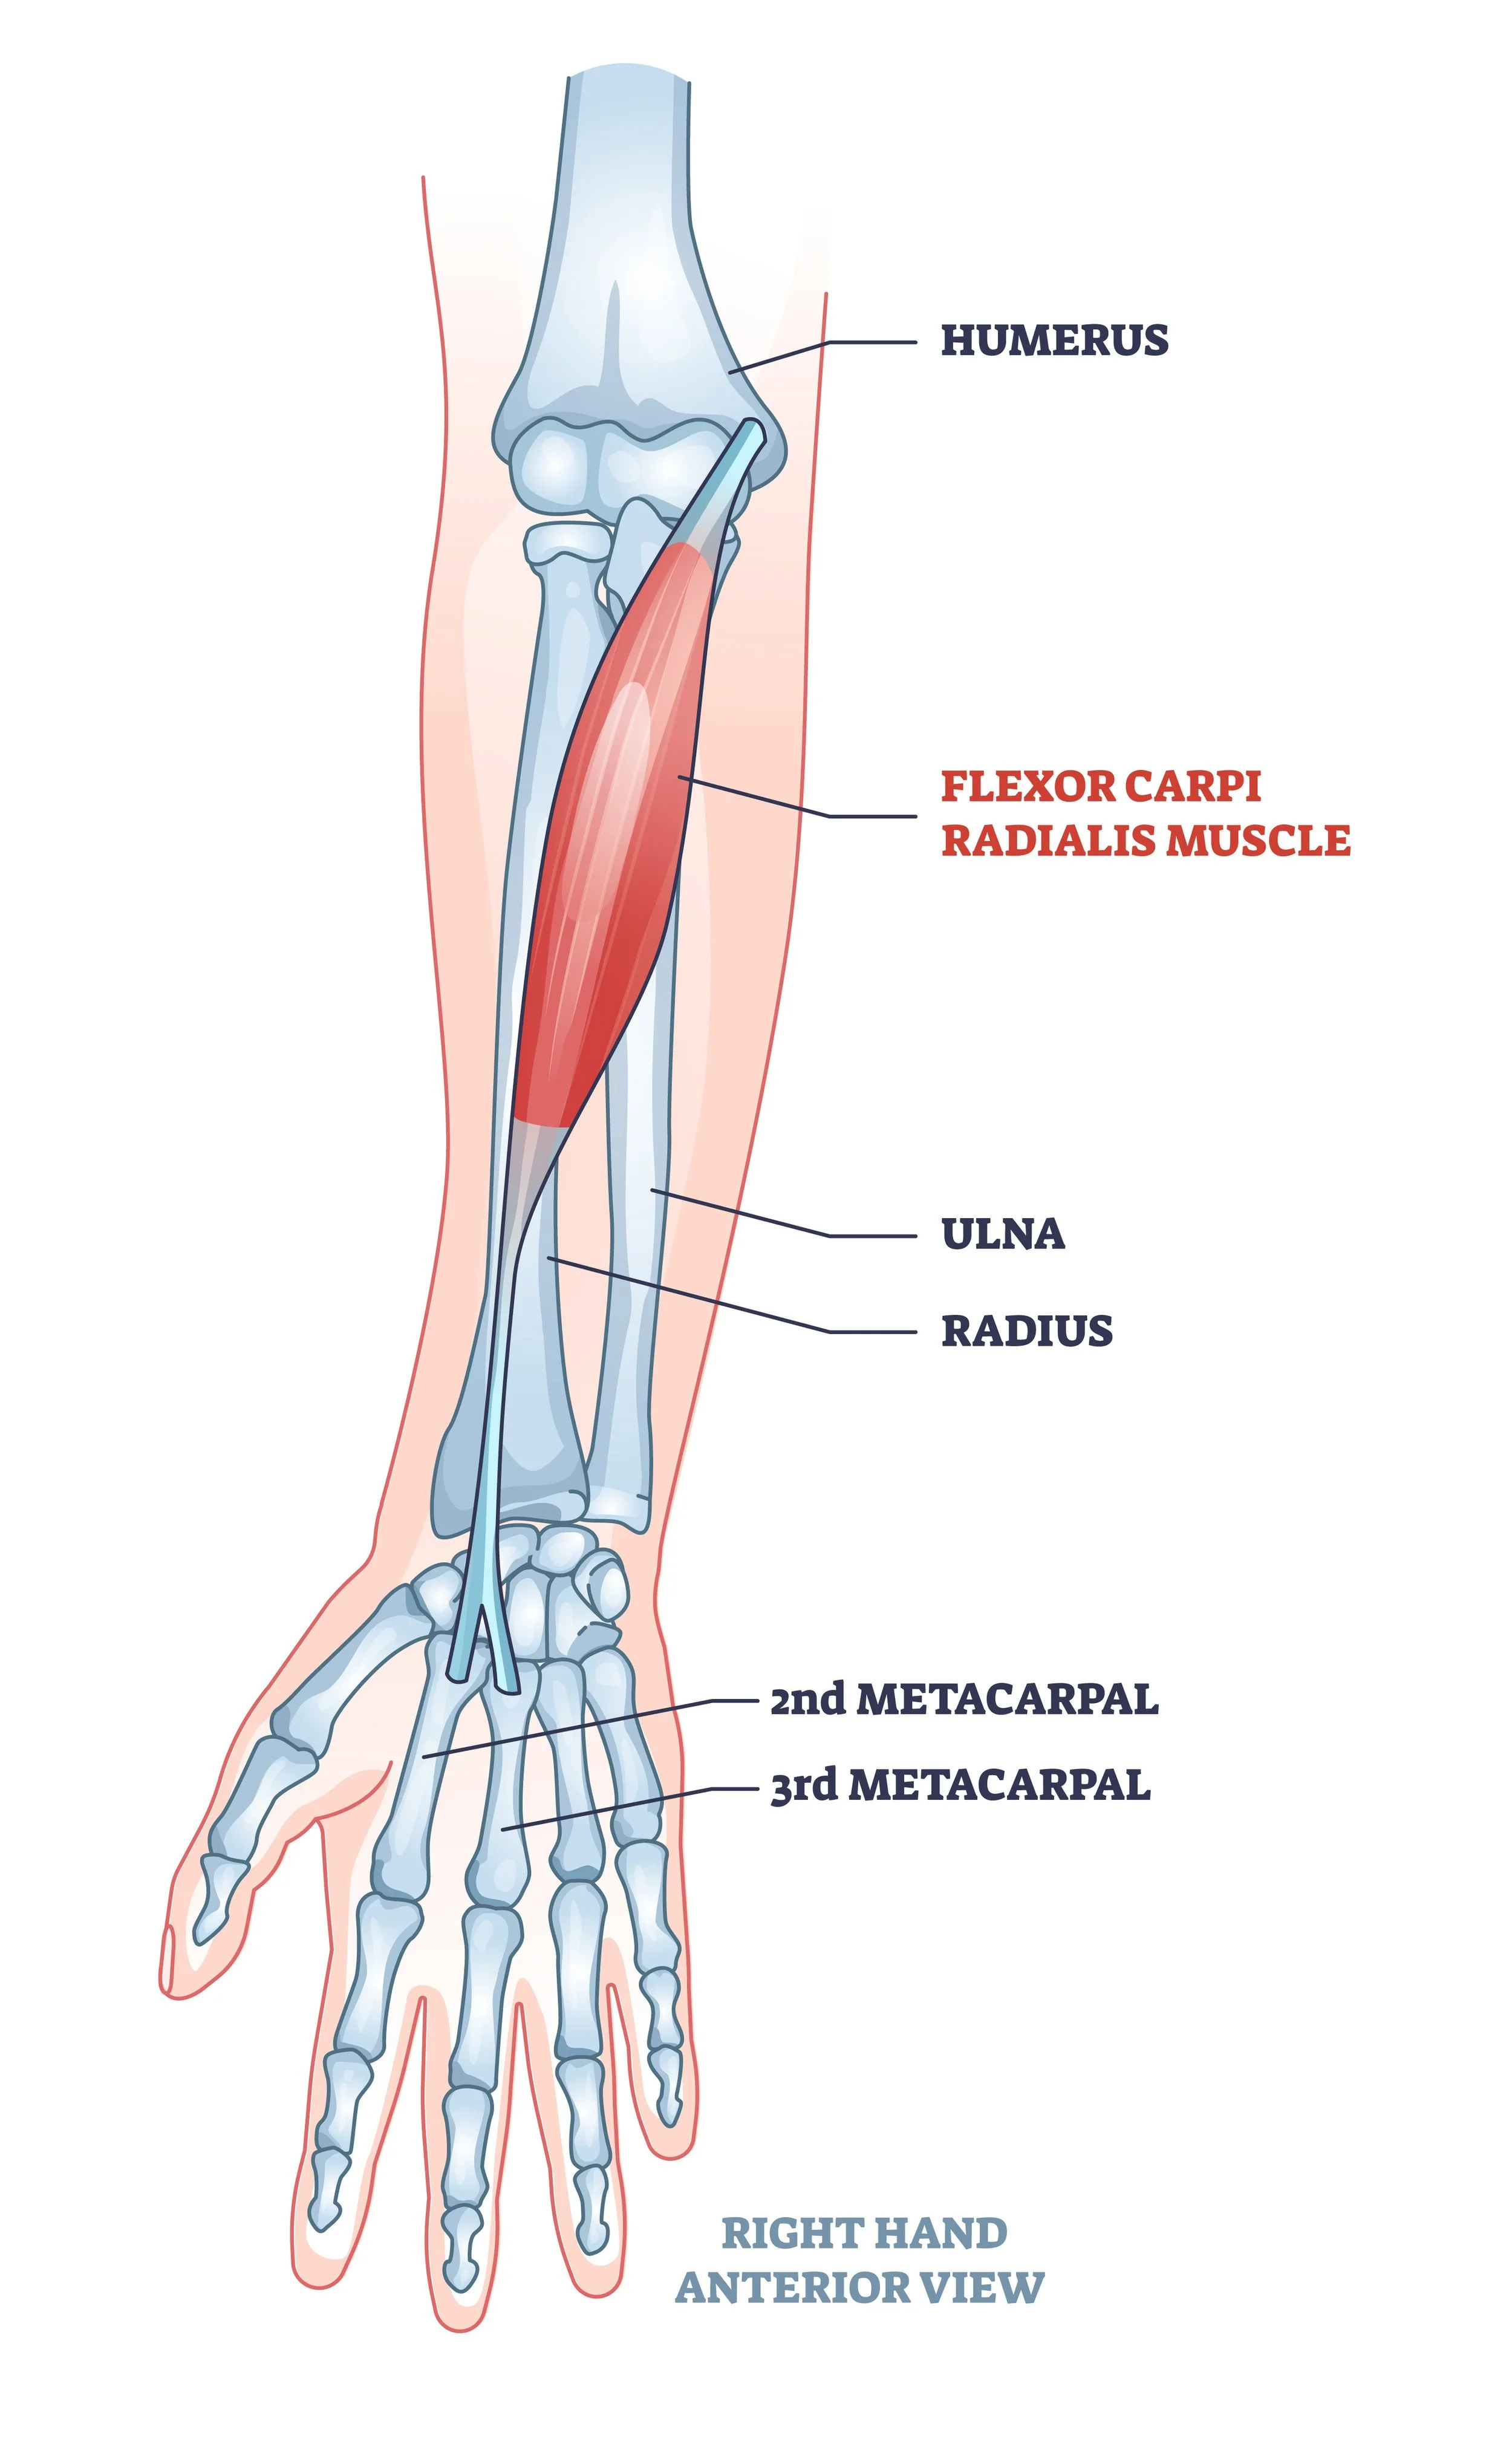

Muscles:

Wrist/Finger Flexors: The group of muscles in charge of flexing the wrist and fingers (heavily utilized during the throwing motion).

Common Flexor tendon: The tendon that connects the flexor muscle group to the inside elbow (medial epicondyle).Ligaments:

Although rest and reduction in throwing is the primary treatment for Little League elbow, physical therapy is a highly recommended supplement to the recovery process. During rehabilitation, physical therapy can help improve the strength of the muscles involved in throwing, such as the wrist flexors, rotator cuff, scapular stabilizers, and the core. Not only can this help prevent atrophy during times of disuse, but it may also help reduce stress levels to the injured elbow once throwing is resumed. Additionally, a baseball-specific PT can help with a safe return to throwing. A proper return-to-throw program will provide the athlete with a safe yet efficient path to high-intensity throwing without running the risk of overexerting the freshly healed elbow.